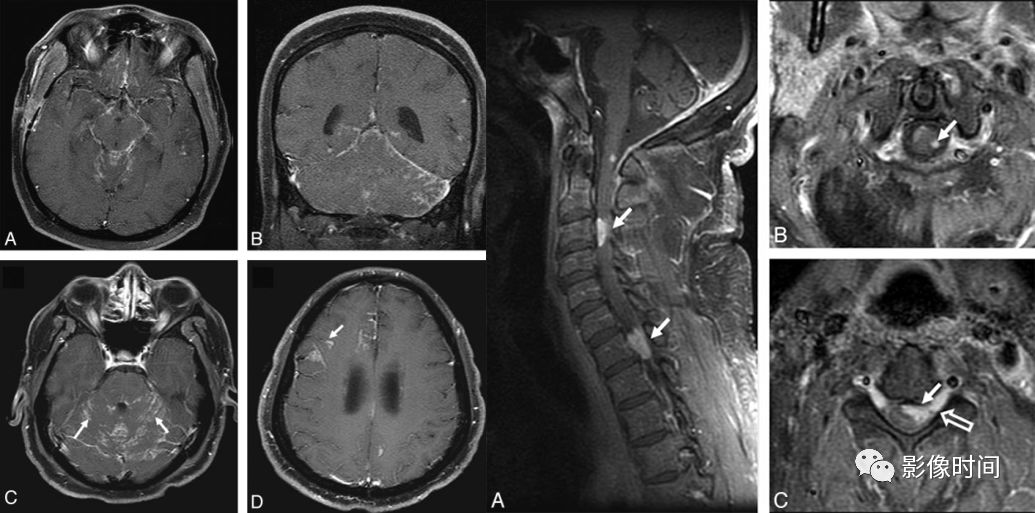

神经脊髓炎谱系疾病(neuromyelitis optica spectrum disorder,NMOSD):是一种由水通道蛋白-4(AQP-4)自身抗体介导的炎性脱髓鞘疾病,青年或中年女性较多见,临床常为双侧视神经炎和脊髓炎导致失明和截瘫,也可累及大脑。

MRI:

脊髓:病灶 T2WI 呈高信号,T1WI 呈稍低信号,急性期出现斑片状或云雾状强化,轴位常位于脊髓中央,长度>3 个椎体长度。亮点征:轴位 T2WI 很高信号的多发斑点,信号高于脑脊液,特异性=97%。

病灶分布于脊髓中央,长度大于3个椎体,亮点征

视神经:双侧视神经广泛受累,病灶长度通常>1/2 视神经长度,优先损害后视通路,包括视神经颅内段、视交叉和视束,急性期 T2WI 视神经肿胀伴明显高信号,T1WI 视神经明显强化,后视通路为主。

后视路受累为主,明显强化

大脑:AQP4 通道是中枢神经系统最丰富的水通道,在室管膜周围、下丘脑和软脑膜下区以及脑干、极后区均有高表达。因此,高表达 AQP4 的特定区域成为 NMO 自身免疫靶点

多发性硬化(Multiple sclerosis,MS)亦是一种严重的中枢神经系统自身免疫脱髓鞘病变,免疫球蛋白分泌 B 细胞和浆细胞的克隆性扩增,可使 CSF 中出现寡克隆带特征。

脊髓:颈髓较常受累,病灶 T2WI 呈高信号,T1WI 呈稍低信号,轴位常分布于前索、侧索或者后索,长轴 ≤ 2 个连续阶段椎体,急性期呈斑片状、结节状或环形强化。

病灶位于侧索、长度小于3个椎体节段

大脑:病灶常呈卵圆形,病灶长轴与侧脑室前后径垂直,沿深髓静脉分布,「Dawson 手指征」

病灶长轴垂直于侧脑室分布